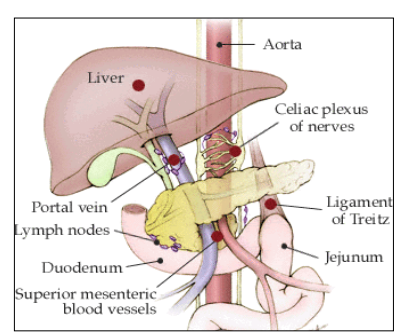

Lower GI bleed = any bleeding distal to the ligament of Treitz

*ligament of Treitz: connects duodenum to the diaphragm and divides it from jejunum